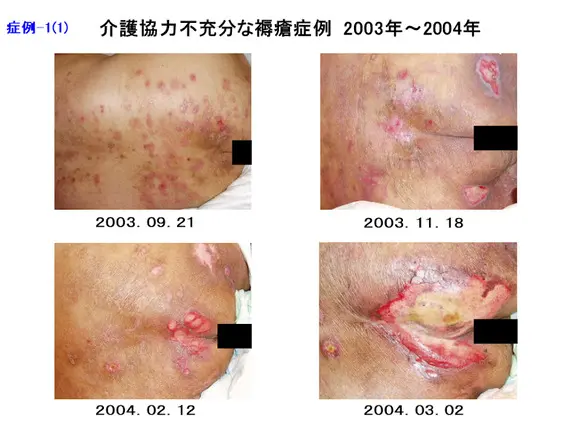

防ぎきれない褥瘡」とは何か?そして今、新名称「不可避褥瘡 UPI 」へ変わった。-最新トピックスを解説します-花王ハイジーンソルーション。